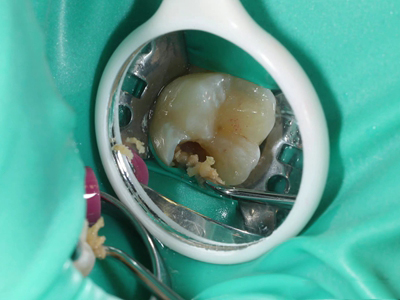

年轻恒牙龋指的是儿童萌出不久的第一恒磨牙龋病和上颌恒切牙龋病,其中第一恒磨牙龋病占年轻恒牙龋的90%,发病早,进展快,可表现为白垩色斑片、点隙窝沟墨浸状龋坏或龋洞。本病的发生和年轻恒牙的特点以及儿童饮食、口腔卫生等因素有关。

年轻恒牙龋好发于第一、二恒磨牙(牙合)面、邻面,上颌中切牙邻面,多为急性龋,龋坏进展快。平滑面的早期龋多为白垩色的斑片,点隙窝沟的早期龋多为浸墨状,表面粗糙。如果早期龋不及时治疗,可逐渐形成大而深的龋洞,易导致牙髓炎和根尖周炎。